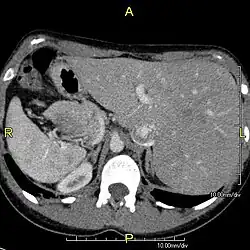

Situs inversus (lat. invertierte Lage) ist der medizinische Ausdruck für das Vollbild einer Heterotaxie, eine seltene, an sich nicht krankhafte Besonderheit der Anatomie, bei der sich die einzelnen Organe spiegelverkehrt jeweils auf der anderen Seite des Körpers befinden. Das Antonym ist der Situs solitus, also die normgerechte Position der Organe im Körper.[1] Synonyme des Situs inversus sind: Inversio viscerum,[2] Situs inversus viscerum, Situs inversus totalis, Situs perversus, Situs transversus, Situs rarior,[3] Situs transversus viscerum,[4] Situs oppositus, Situs inversus completus.

Situs inversus bei Menschen

Der Situs inversus (viscerum) tritt bei etwa einem von 8.000 bis 25.000 Menschen und bei der Hälfte der Menschen mit primärer ciliärer Dyskinesie (Kartagener-Syndrom) auf.[6] Bei Menschen mit dieser Heterotaxie befindet sich die Leber beispielsweise auf der linken und im Gegensatz dazu die Milz auf der rechten Seite. Ein auffälliger Anstieg von Fällen wurde einige Monate nach der Aufhebung der Zero-COVID-19-Politik in China beobachtet, was mit einem Anstieg von SARS-CoV-2-Infektionen zusammenfiel. Seltene klinische Hinweise zeigen eine mögliche Folge einer SARS-CoV-2-Infektion bei Schwangeren, speziell in den Schwangerschaftswochen 4–6, dem Entwicklungszeitraum für die Organe des Fötus.[7]

Um eine Appendizitis (Blinddarmentzündung) nicht zu übersehen, muss bei Schmerzen im linken Unterbauch auch an die Möglichkeit eines Situs inversus gedacht werden.